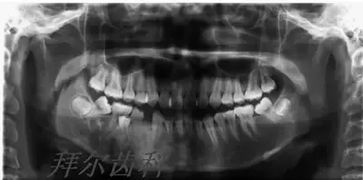

牙拔除后半小時,吐出壓迫的棉卷,如仍有明顯出血時,即稱為拔牙后出血。拔牙后出血絕大多數(shù)為局部因素,少數(shù)為全身因素引起。但不論什么原因引起的出血,都應該首先注意病員的全身情況,詢問出血情況,估計出血量,注意脈搏、血壓的變化。根據(jù)情況,決定是否輸入液體,甚至輸血。了解全身情況以后,再進行局部檢查,根據(jù)出血原因進行處理。

對全身因素引起的出血,如血友病等,應以預防為主,必要時應同內(nèi)科醫(yī)生進一步診治。局部因素引起的出血,如牙槽窩內(nèi)殘留炎性肉芽組織、軟組織撕裂、牙槽骨骨折、凝血塊脫落、牙槽內(nèi)小血管或下牙槽血管等知名血管破裂。查明出血原因后,即可對癥進行處理。牙槽窩內(nèi)有肉芽組織時,應徹底清除,才能止血。牙齦有撕裂傷時,應予以縫合。多數(shù)病員的拔牙創(chuàng),可看到血凝塊高出牙槽窩并滲血,可用紗布將高出牙槽窩的血塊清除,置止血粉后,再用紗布卷壓迫。如不能止血,再將兩側牙齦作水平褥式縫合,可使拔牙創(chuàng)兩側粘骨膜瓣緊張而減少血運,有助于止血。這是因為多數(shù)出血不是來自牙槽窩,而是來自周圍的軟組織??p后壓迫5分鐘,如出血仍不停止,應用明膠海綿、止血粉等放入牙槽窩,再咬紗卷壓迫止血。對于牙槽窩內(nèi)出血,用上述方法不能止血,可在局麻下清除拔牙窩內(nèi)血塊,用一長碘仿砂條緊密填塞后加壓,??墒盏街寡Ч?。處理完畢后,用紗布浸冷水拭凈口內(nèi)血塊,以防病員感到不適而漱口,這會促使創(chuàng)口再度出血。碘仿砂條在1周后取出。